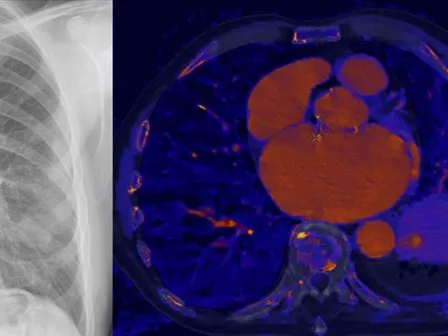

The purpose of this online chest radiology fellowship is to give a comprehensive course in the diagnostic work-up of lung cancer. This includes the presentation of Fleischner Society and British Thoracic Society algorithms for the work-up of solitary pulmonary lung nodules. In addition, the course will give hands-on experience in the usage of TNM 8 classification of lung cancer. Finally, the course will introduce the usage of spectral CT in the workup of lung cancer.